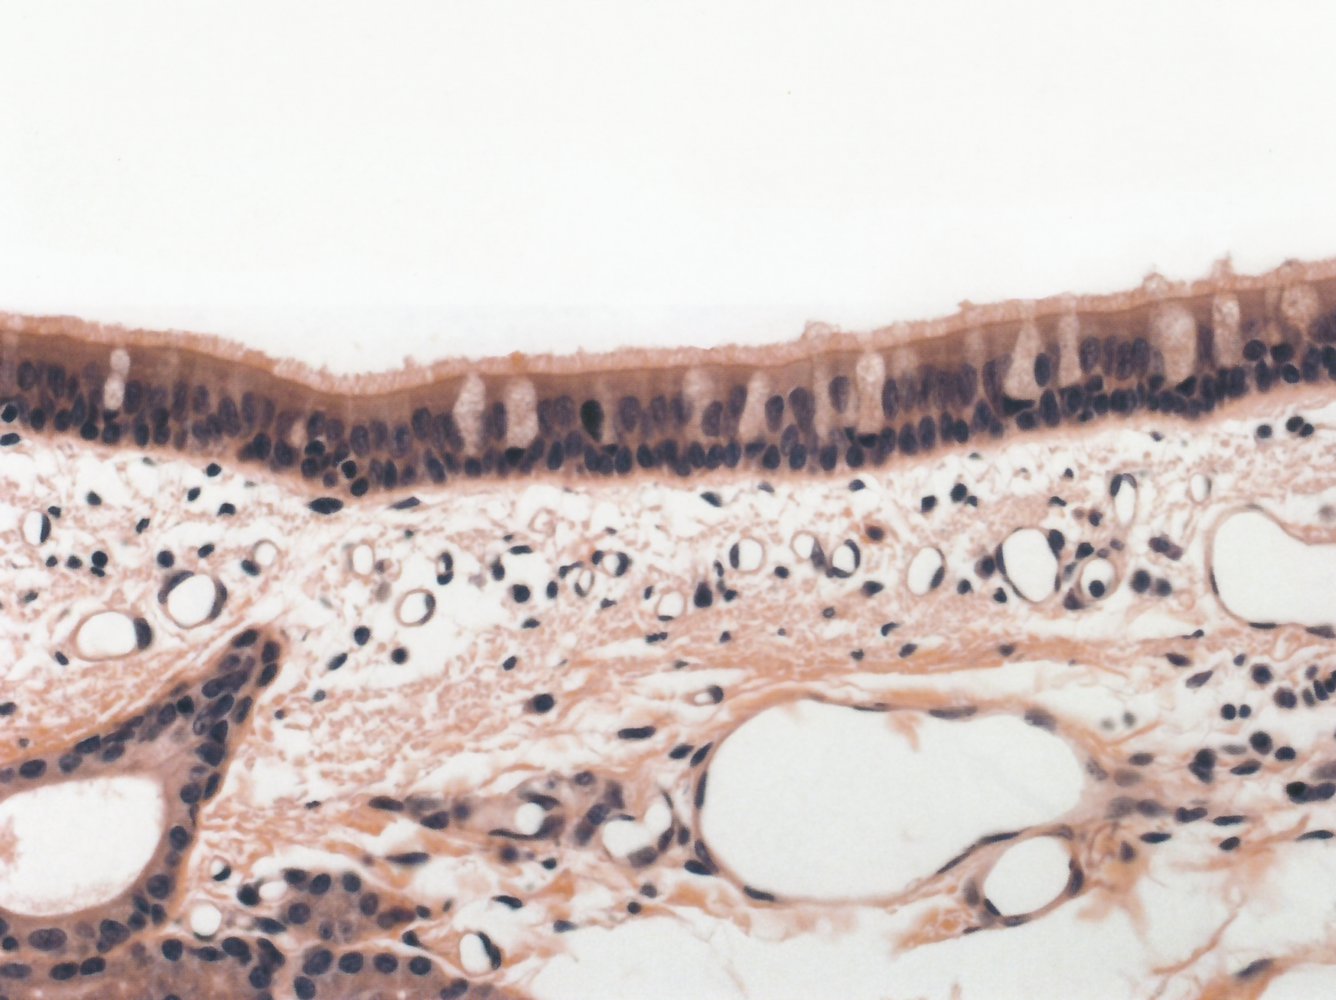

• Pseudostratified ciliated columnar epithelium: important for mucociliary clearance

• Goblet cells

• Bronchioles: simple ciliated columnar epithelium; enclosed by smooth muscle

• Terminal bronchioles: simple ciliated cuboidal epithelium; smooth muscle

Respiratory zone [1]

Respiratory bronchioles

Respiratory bronchioles contain simple (non-ciliated) cuboidal and squamous epithelium and smooth muscle.